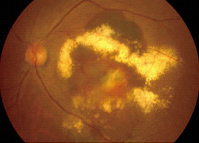

- 3.眼底検査

- 細隙灯顕微鏡(さいげきとうけんびきょう)を用いるなどして、眼底にある網膜の状態を調べます。細隙灯顕微鏡から、眼底に細くて強い光を当て、病気の所見を拡大して調べます。滲出型加齢黄斑変性では、出血、網膜のむくみなどが観察できます。

滲出型加齢黄斑変性症の眼底写真